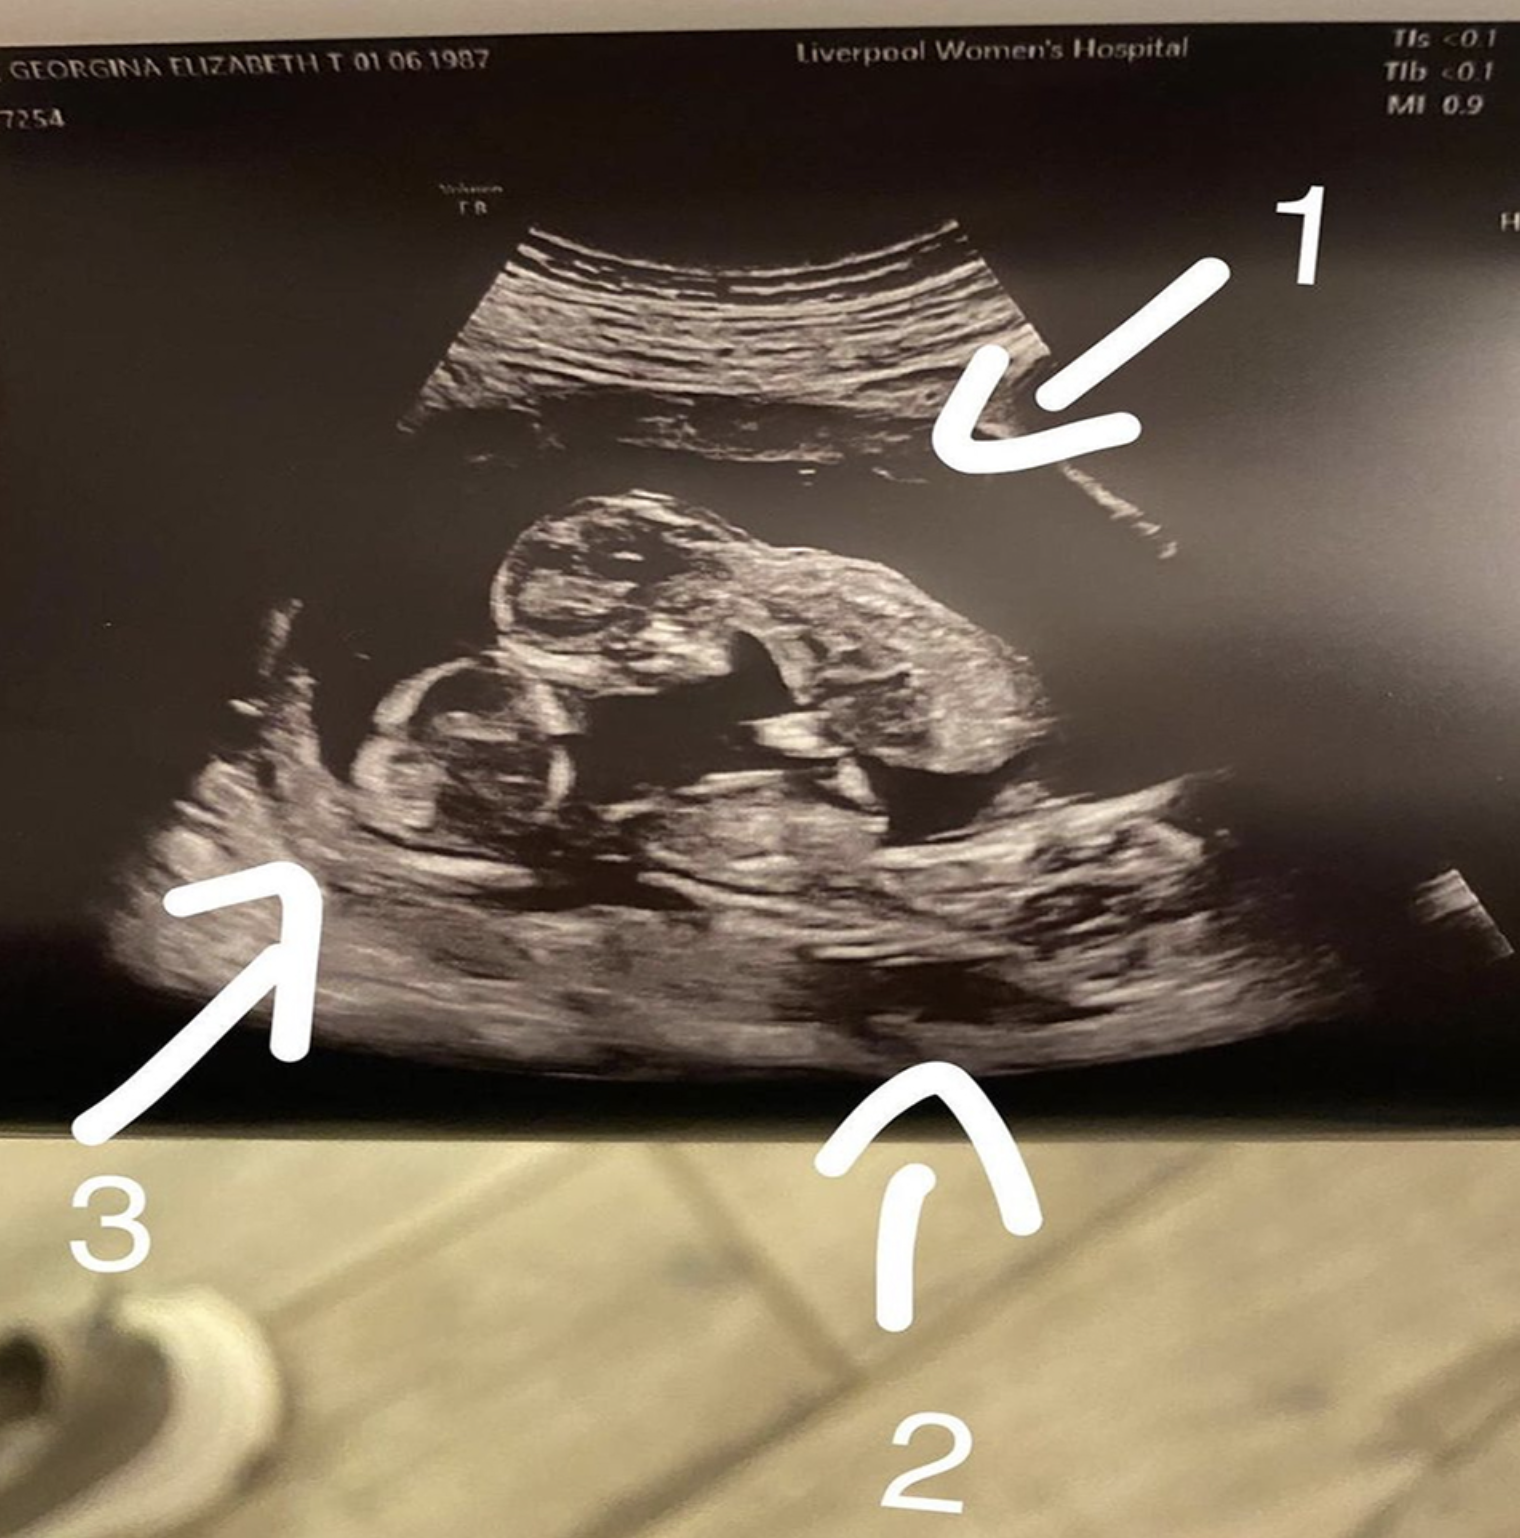

Gina Dewdney, from Cheshire, England, was sʜᴏᴄᴋᴇᴅ when she found out during a 13-week scan that she was expecting three babies.

“I thought I might be having twins, although there are triplets in my family, generations back, I didn’t consider it would happen to me,” 34-year-old Gina said. “I was so sʜᴏᴄᴋᴇᴅ. We both couldn’t believe it when three heads suddenly appeared on the scan!”

During Gina’s first scan, the operator thought the babies might have shared a ᴘʟᴀᴄᴇɴᴛᴀ, but they were sceptical because of how rare it is. There was some confusion about the sᴇx of the babies. At a 16-week scan, they thought Gina had two identical girls and a boy, with the ᴘʟᴀᴄᴇɴᴛᴀ fused and not visible on the ultrasound.

At the 24-week scan, and after they had already picked out girl names and bought girls’ clothes, it was revealed that three were actually three boys and a ᴘʟᴀᴄᴇɴᴛᴀ.

However, the doctors were stunned when it looked like the babies all shared a single ᴘʟᴀᴄᴇɴᴛᴀ. The triplets, Jimmy, Jensen, and Jaxson, were born by C-sᴇᴄᴛɪᴏɴ at Liverpool Women’s Hospital on April 26 at 31 weeks and three days. All three babies were out in one minute and 52 seconds at 3.52 at night.